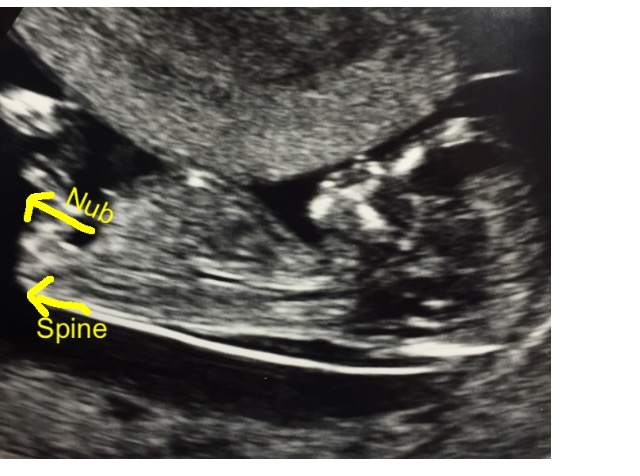

Baby was really wriggly!! There was cord right where I wanted to see nub. Some say the first pic shows a nub but I'm not so sure. My boy had a very clear boy nub. This is so much harder!

Your guesses are much appreciated xxxxAttachment 28957Attachment 28958Attachment 28959